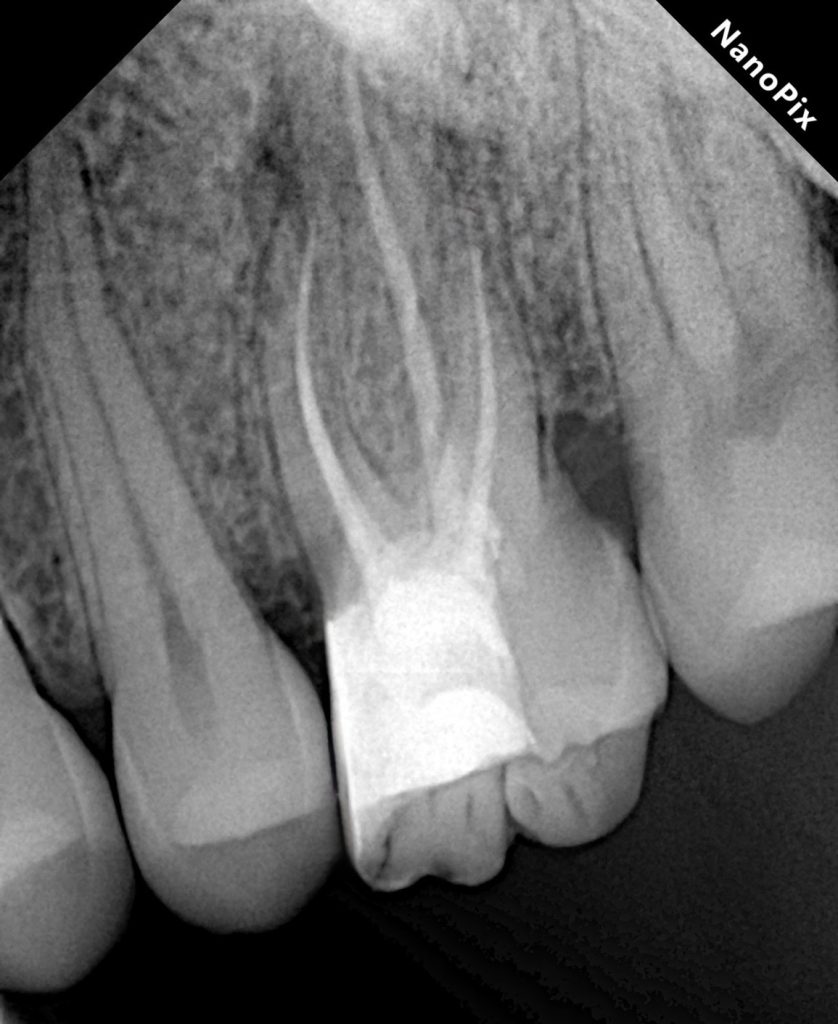

Obturation

Following complete drying of the canal system, obturation was performed to achieve a dense, three-dimensional seal. All canals, including MB2, were obturated to full working length with confirmed radiographic adaptation.

A definitive coronal seal was established immediately after obturation.

The final result demonstrated:

- Successful negotiation and obturation of MB2

- Adequate coronal seal

- Reinforced cuspal structure

- Stable occlusion with functional anatomy

The tooth was returned to function with improved structural prognosis and reduced risk of fracture.